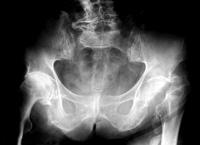

第三步:X光脊椎照片诊断

脊医会观察脊椎X光片各椎间的变化,脊柱轴线变异情况,椎体后缘联线变异情况。脊椎错位时会出现的仰位、倾位、仰旋、倾旋和侧旋等改变。各椎间关节形态或位移都属颈椎关节错位的表现。观察各椎间盘变性、椎间关节骨质增生,各韧带钙化的部位、程度等。并与第一、二步定位诊断结合分析,作出最后的诊断结果。

X光脊椎照片诊断的重要性:

1、排除脊柱肿瘤、结核、骨折、脱位及类风湿、痛风等病症。

2、分析椎间关节错位的部位及方向。

3、分析椎间盘变化程度,骨质增生部位与症状部位的关系。